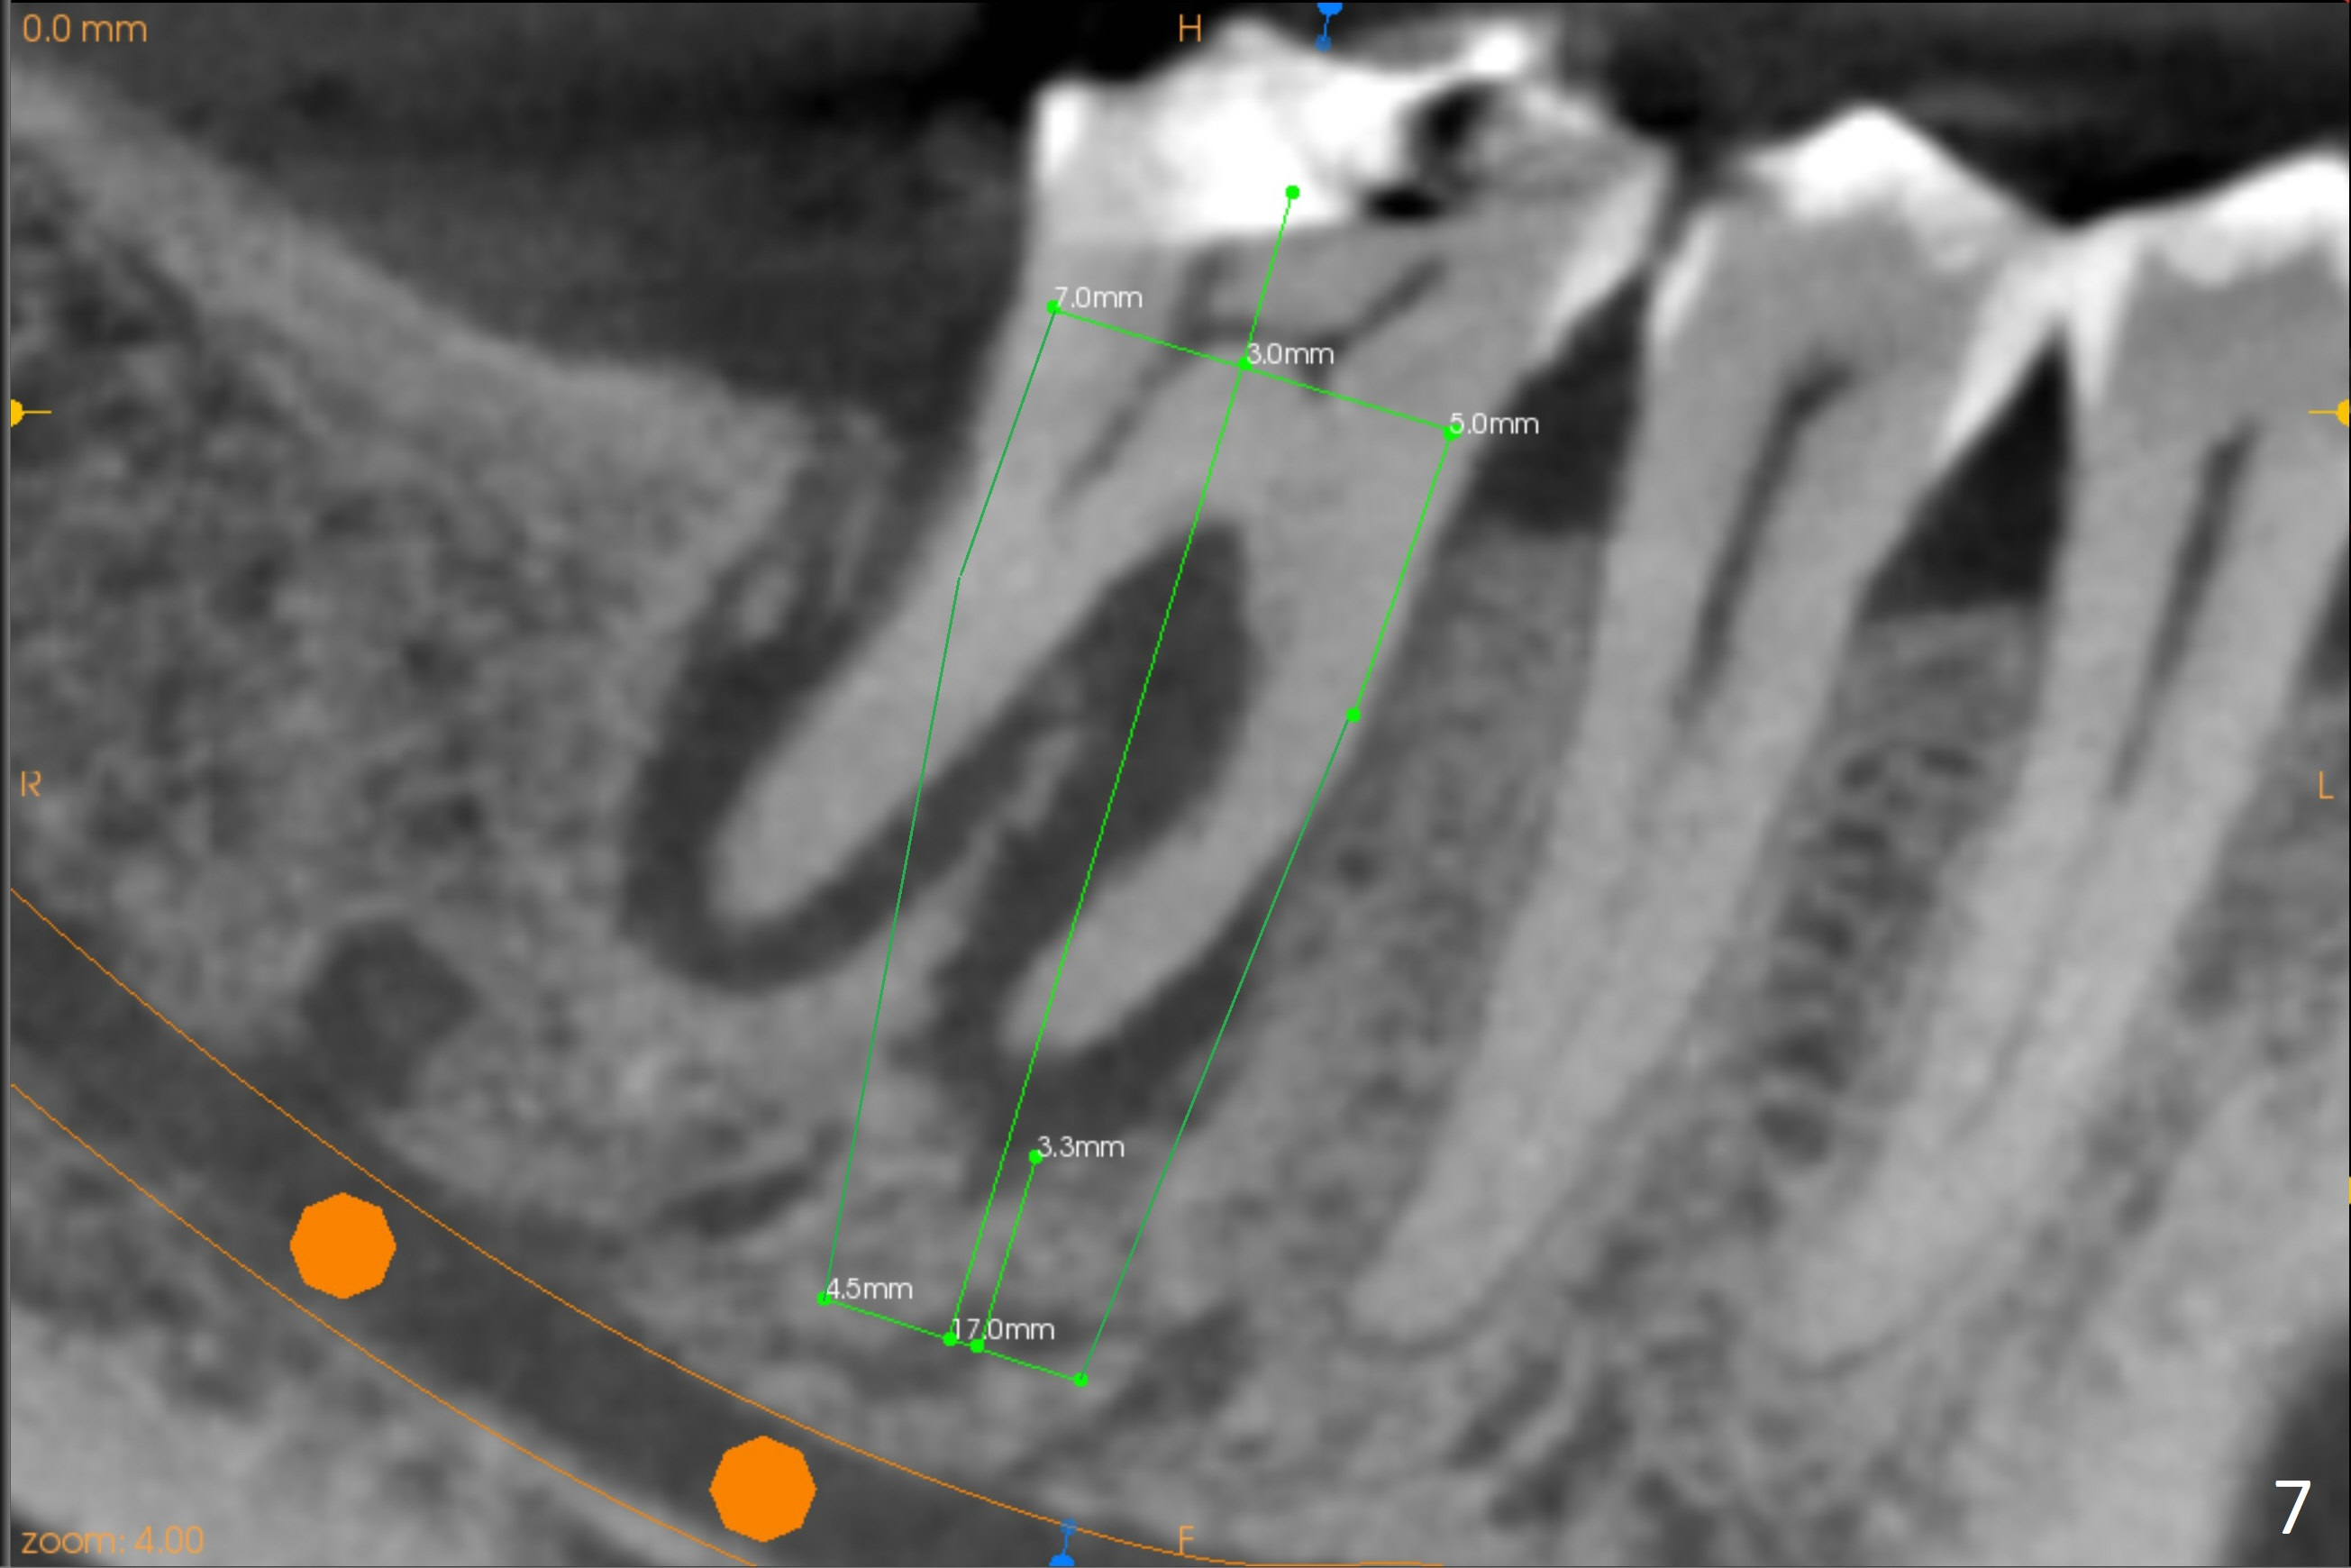

A 71-year-old woman (bruxer) wants to remove the tooth #30 (occlusal trauma, possible root fracture) for implant following the one at #14 (Fig.1). IBS abutment screw tends to loosen in functioning if the implant is placed too deep and/or off the longitudinal axis. If these two conditions are not controlled well, switch to a large tissue-level implant. A drawback of placing the implant in the septum is that the mesial margin of the abutment (Fig.2 pink) is subcrestal. If the implant is placed in the mesial socket (Fig.5 red line), the imagined abutment margin plane (white line) is parallel to the mesiodistal crests. Initial osteotomy entry point in the mesial socket and trajectory should be adjusted intraop (compare Fig.6 and 7) so that the apex of the implant will not be too close to the apex of the tooth #29 (to avoid truncating the neurovascular supply to the tooth (Fig.6 red arrowheads)) at the same time the abutment inclination is not too compromised (Fig.7). To prevent pressure upon the buccal (Fig.4 B) plate, osteotomy should be slightly lingual and/or the diameter of the implant is to be < 7 mm. Use a 3 mm unipost for provisional and probably 5 mm one for definitive restoration. Apply bonding to the post if the implant is 6 mm or less. The provisional margin should be wide and deep for deep margin and easy impression later. Use IS drills with 4 mm stopper for osteotomy if the septum is absent. Prepare Rongeur and surgical handpiece to remove the remaining septum if needed. Be wary of the distally curved root tip of #29. In fact there is a mesiodistal crack line (Fig.8 arrowheads) with buccal recession (Fig.9, 2 weeks preop).